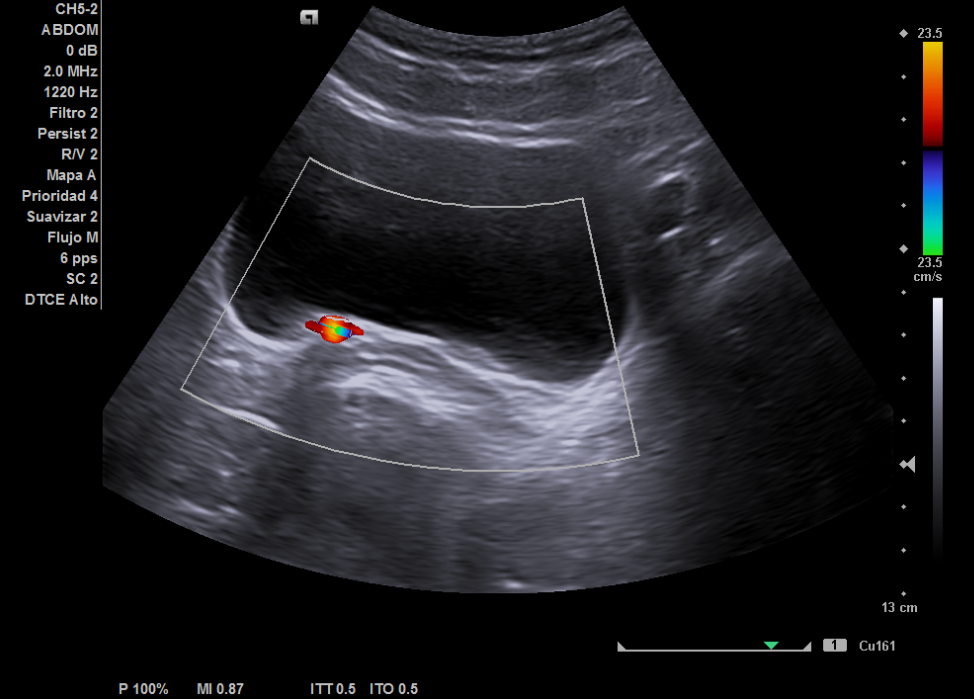

Ecografía: hígado de tamaño y ecoestructura normal, sin evidenciar masas focales. No se aprecia dilatación de las vías biliares. Vesícula sin litiasis. Páncreas visualizado parcialmente, sin evidenciar masas. Bazo de tamaño y ecoestructura normal. Los riñones son de tamaño, forma y ecoestructura normal, con buena diferenciación parénquima-seno y grosor cortical conservado, sin dilatación de vías excretoras ni clara imagen de litiasis. Vejiga distendida de aspecto normal, visualizando dudosas litiasis en las uniones vesico-ureterales.

La ecografía en el centro de salud permitió descartar dilatación pielocalicial o litiasis renal y orientó el diagnóstico hacia posibles secuelas del tratamiento endoscópico previo (STING), mejorando el manejo de la paciente en Atención Primaria. Además, aceleró los tiempos diagnósticos al posibilitar la solicitud de un TAC y una derivación más dirigida al especialista en Urología. Finalmente, cabe destacar que todo ello conlleva a la mejora de la relación médico-paciente.